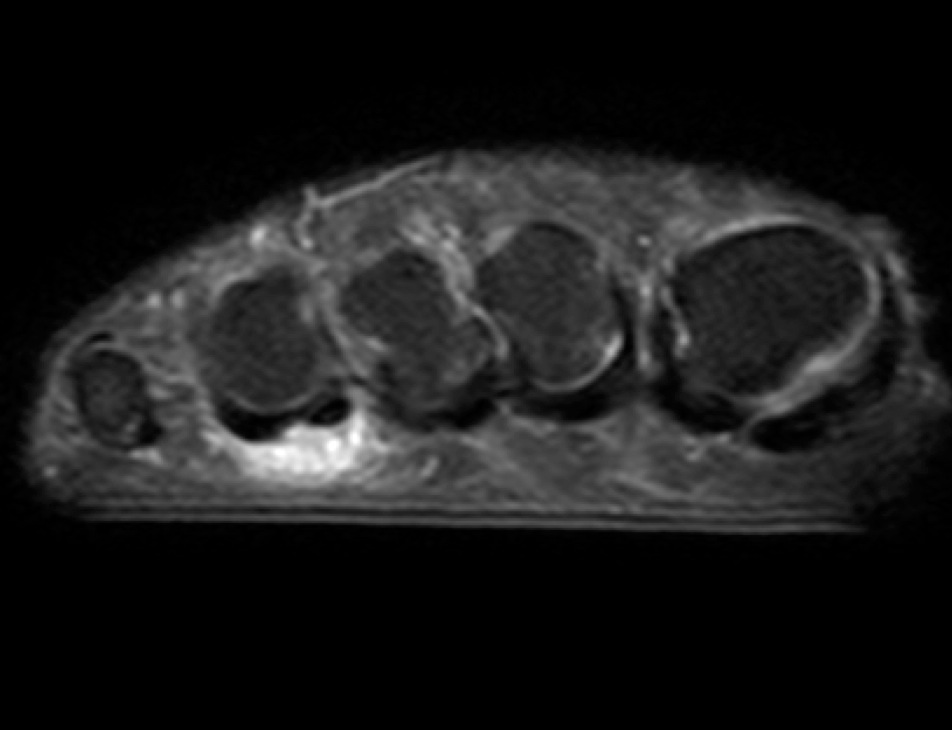

Figure 4 for case Advential bursitis

Figure 4